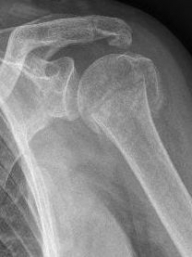

Proximaler Oberarmbruch5Proximaler Oberarmbruch6

Picture: Here is a subcapital upper arm break in a young woman. An angle stable plate osteosynthesis was performed to stabilize the head in correct position to the humeral shaft and shoulder joint. Especially in young patients, We strive to treat non-invasively and as gently as possible. This possibility is often due to the bone quality in young as opposed to older people.